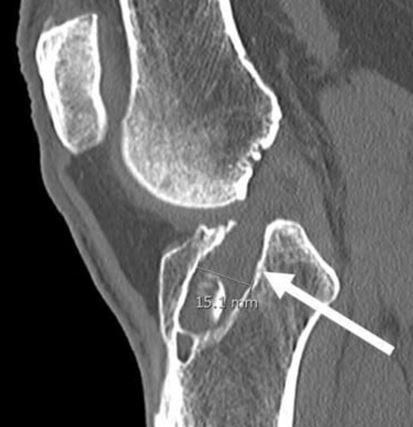

X-rays can detect loosening and osteolysis (bone erosion), as well as component wear, fracture, and malposition.

- Improper tunnel placement during initial surgery which can lead to gradual ligament tear